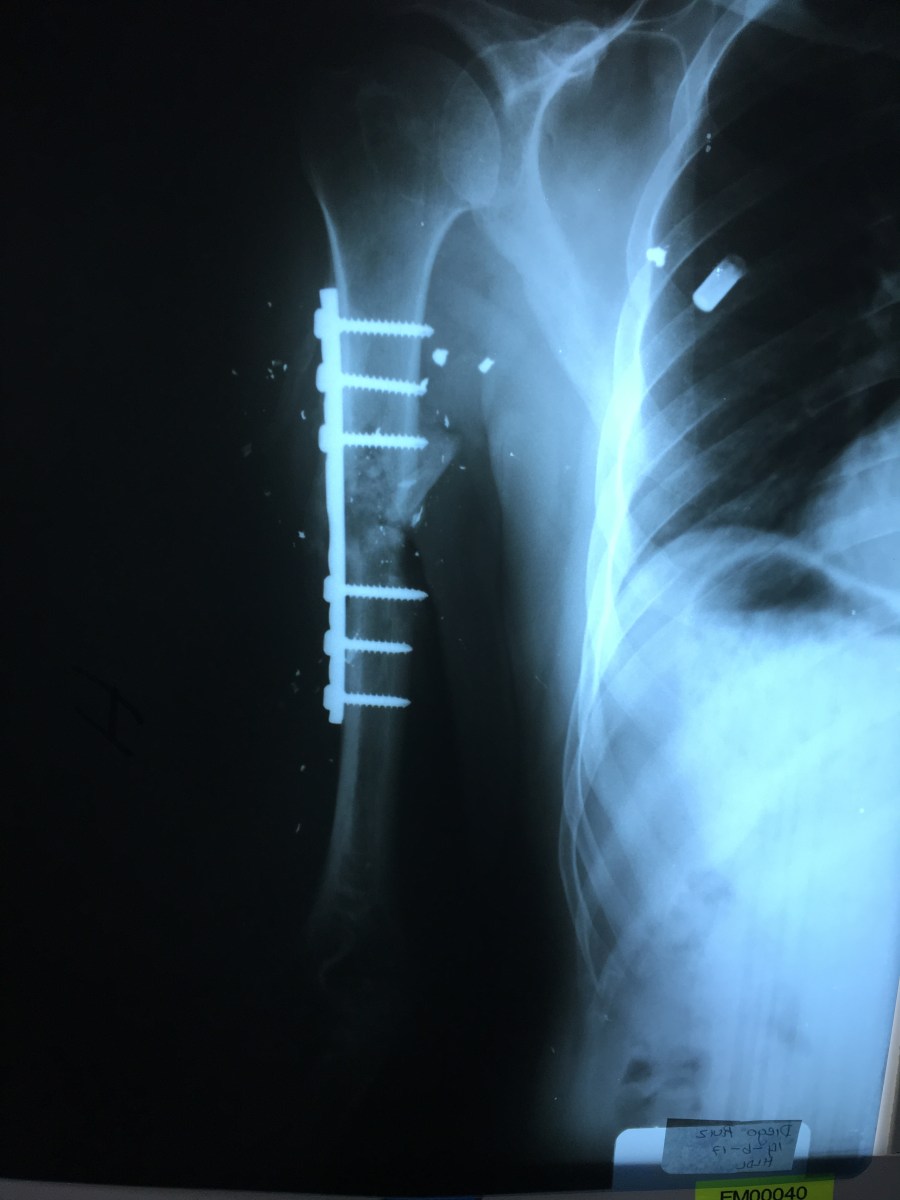

Donny V